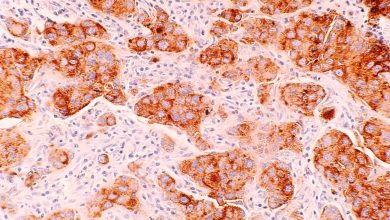

VCP é um gene essencial para KRAS-mutante PDAC. Crédito: 2023 Lee et al. Um novo trabalho de pesquisa, intitulado “VCP/p97,…

Displasia de alto grau (carcinoma in situ) no colo do útero. O epitélio anormal está se estendendo para uma glândula…